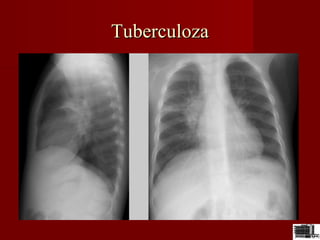

TuberculozaTuberculoza